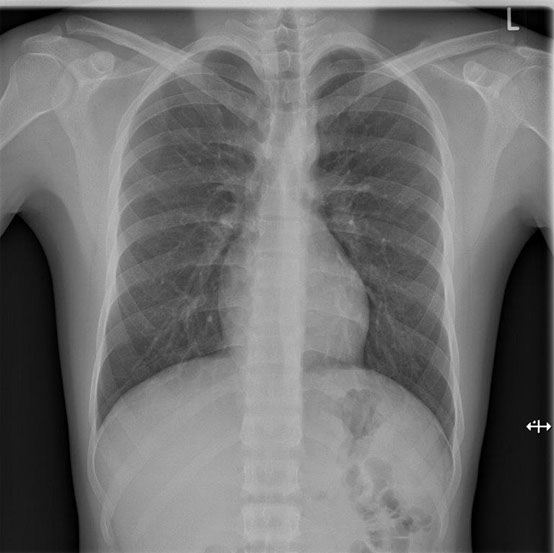

Herz-/Lungenröntgen (Thorax-Röntgen)

Die Untersuchung muss mit tiefer Einatmung (Inspiration) durchgeführt werden. Dies erlaubt eine bessere Beurteilbarkeit der Lunge. Es ist auch wichtig, dass Sie sich während der Aufnahme nicht bewegen. Es werden zwei Aufnahmen im Stehen gemacht. Im Anschluss an das Röntgen wird von der Radiotechnologin die Bildqualität geprüft und erfolgt danach die Befundung durch den Radiologen.